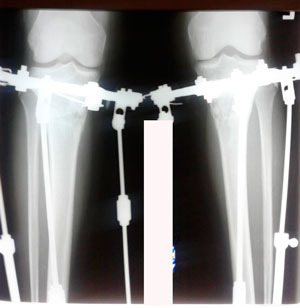

Дата операции - 19.03.2020

Дата снятия аппаратов - 26.06.2020

image-26-06-20-12-43-1.jpg

image-26-06-20-12-43.jpg